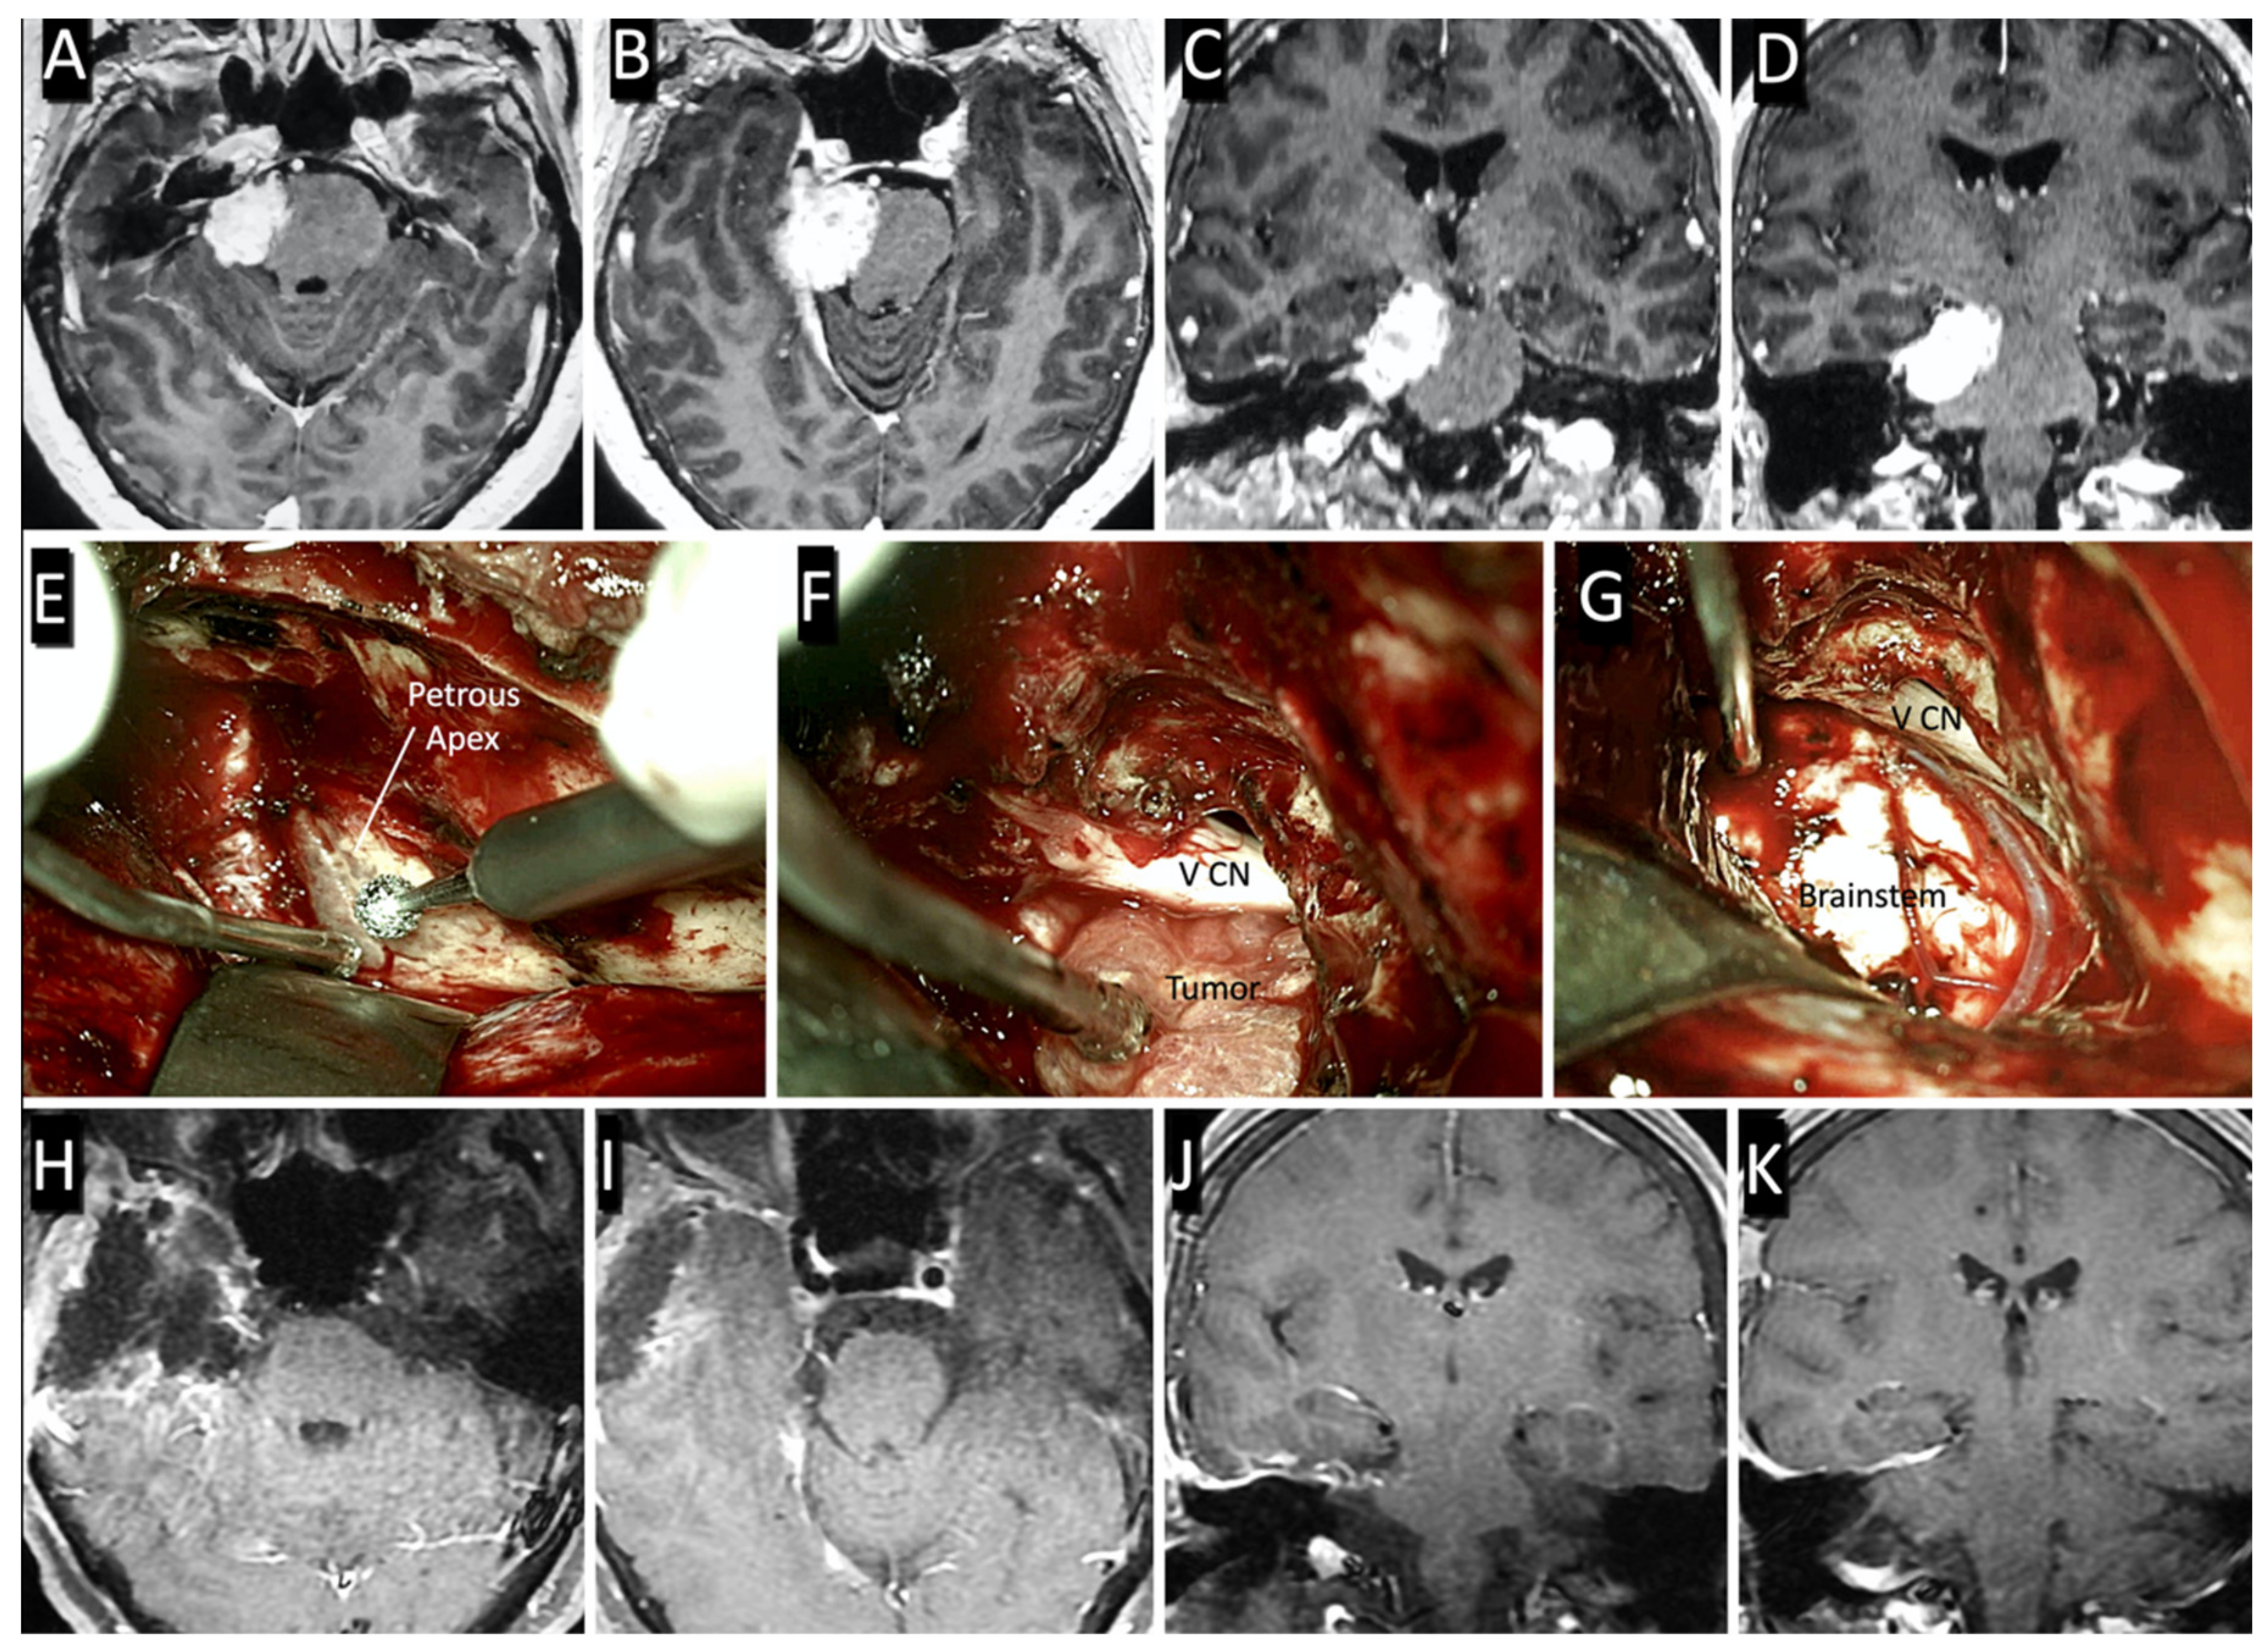

2. Materials and Methods

3.2. Surgical Case